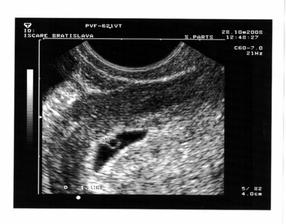

3.11.2008 - sme 7tt+1, máme 5,1 mm a prvýkrát potvrdená akcia srdiečka 🙂